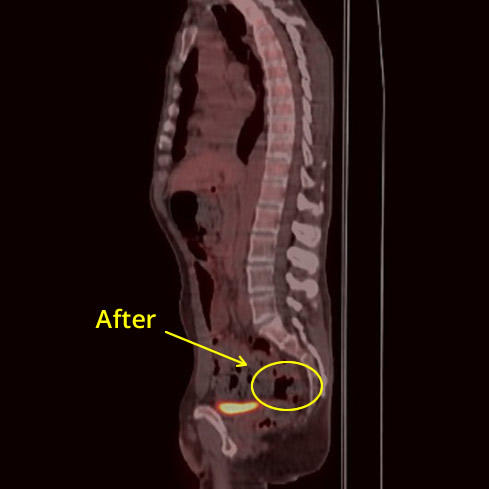

Colon CXR Before

Colon CXR After